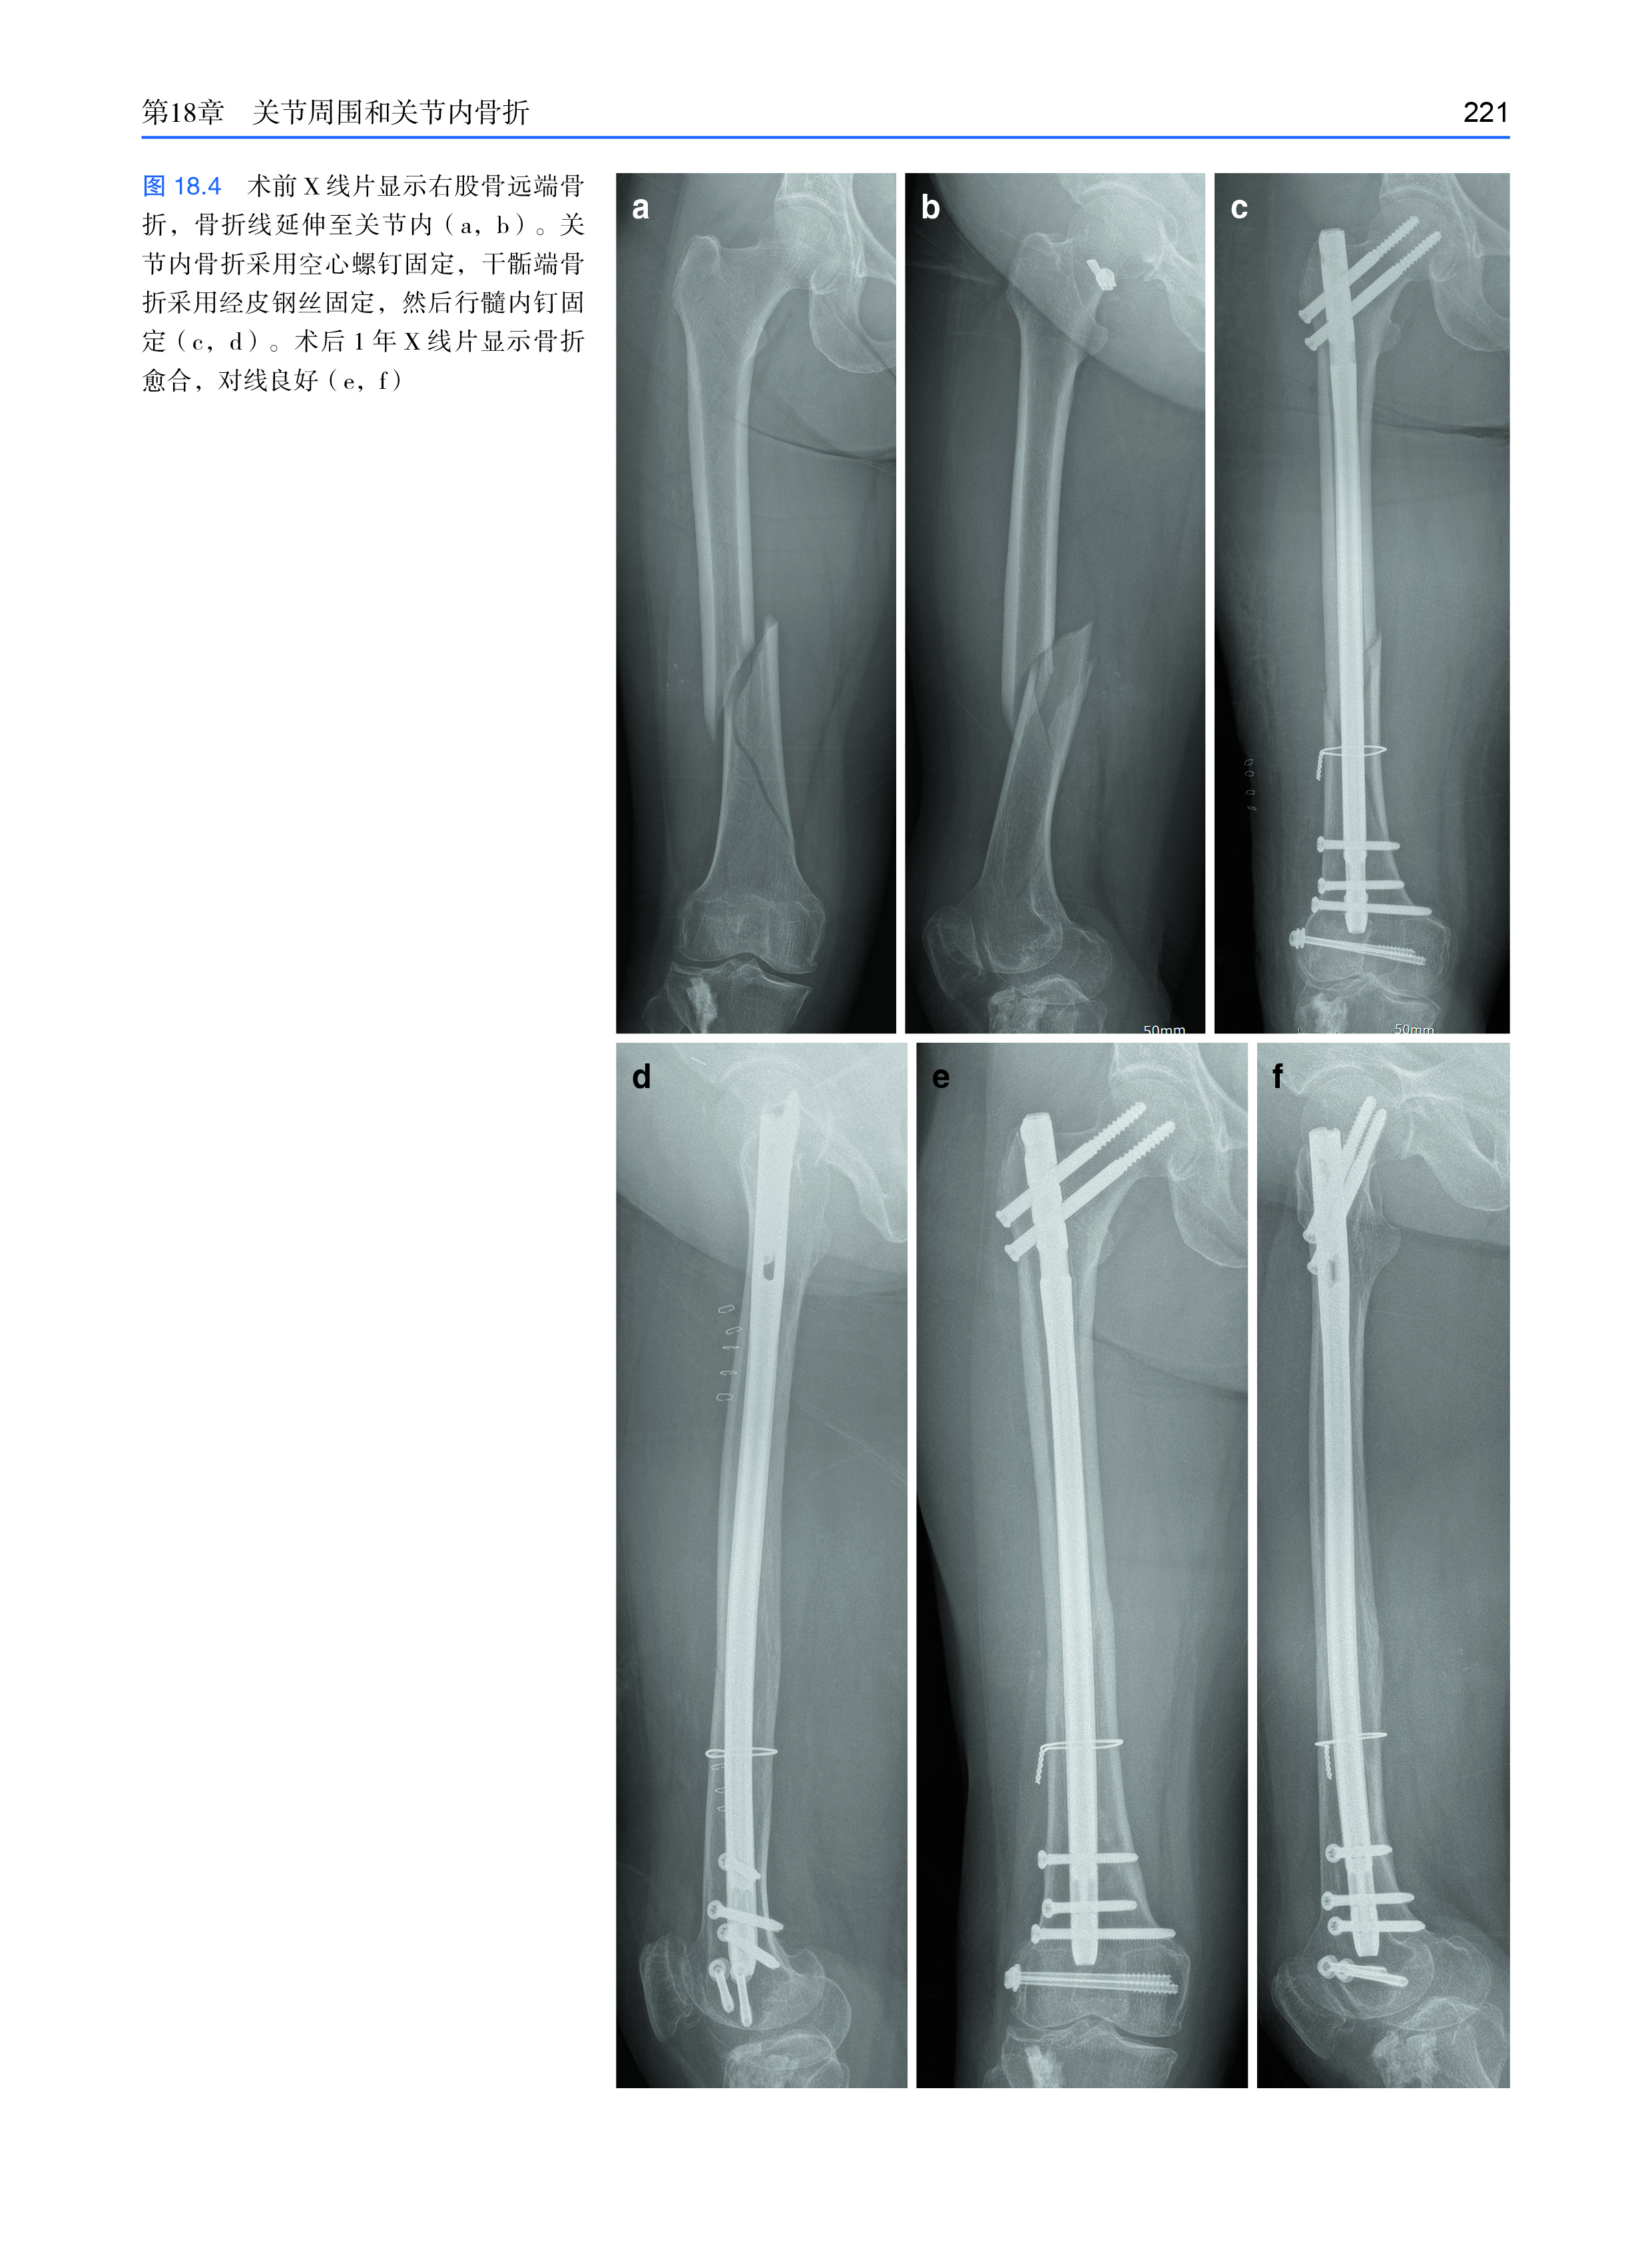

页 数:296

全书共分五章,开篇介绍了与骨骼和关节相关的应力和应变,以及它们与骨折和骨折愈合的关系。第二部分讨论了外固定治疗骨干和关节周围骨折、肢体延长和畸形矫正的生物力学原理。第三部分讨论了尺骨鹰嘴骨折和髌骨骨折的张力带连接,第四部分讨论了锁定钢板和非锁定钢板。最后一章介绍各种骨折和骨不连的髓内钉的生物力学原理,以及关节固定术等。